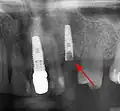

Потеря костной массы (периимплантит) на имплантатах более 7 лет у заядлого курильщика

• с помощью рентгенографии изучаются качество и плотность костной ткани;